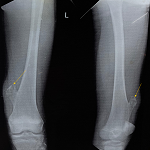

Exostosis of distal femur: benign bone tumor

Aishwarya Borhade, Pratik Phansopkar

PAMJ-CM. 2025; 19: 11. Published 24 October 2025